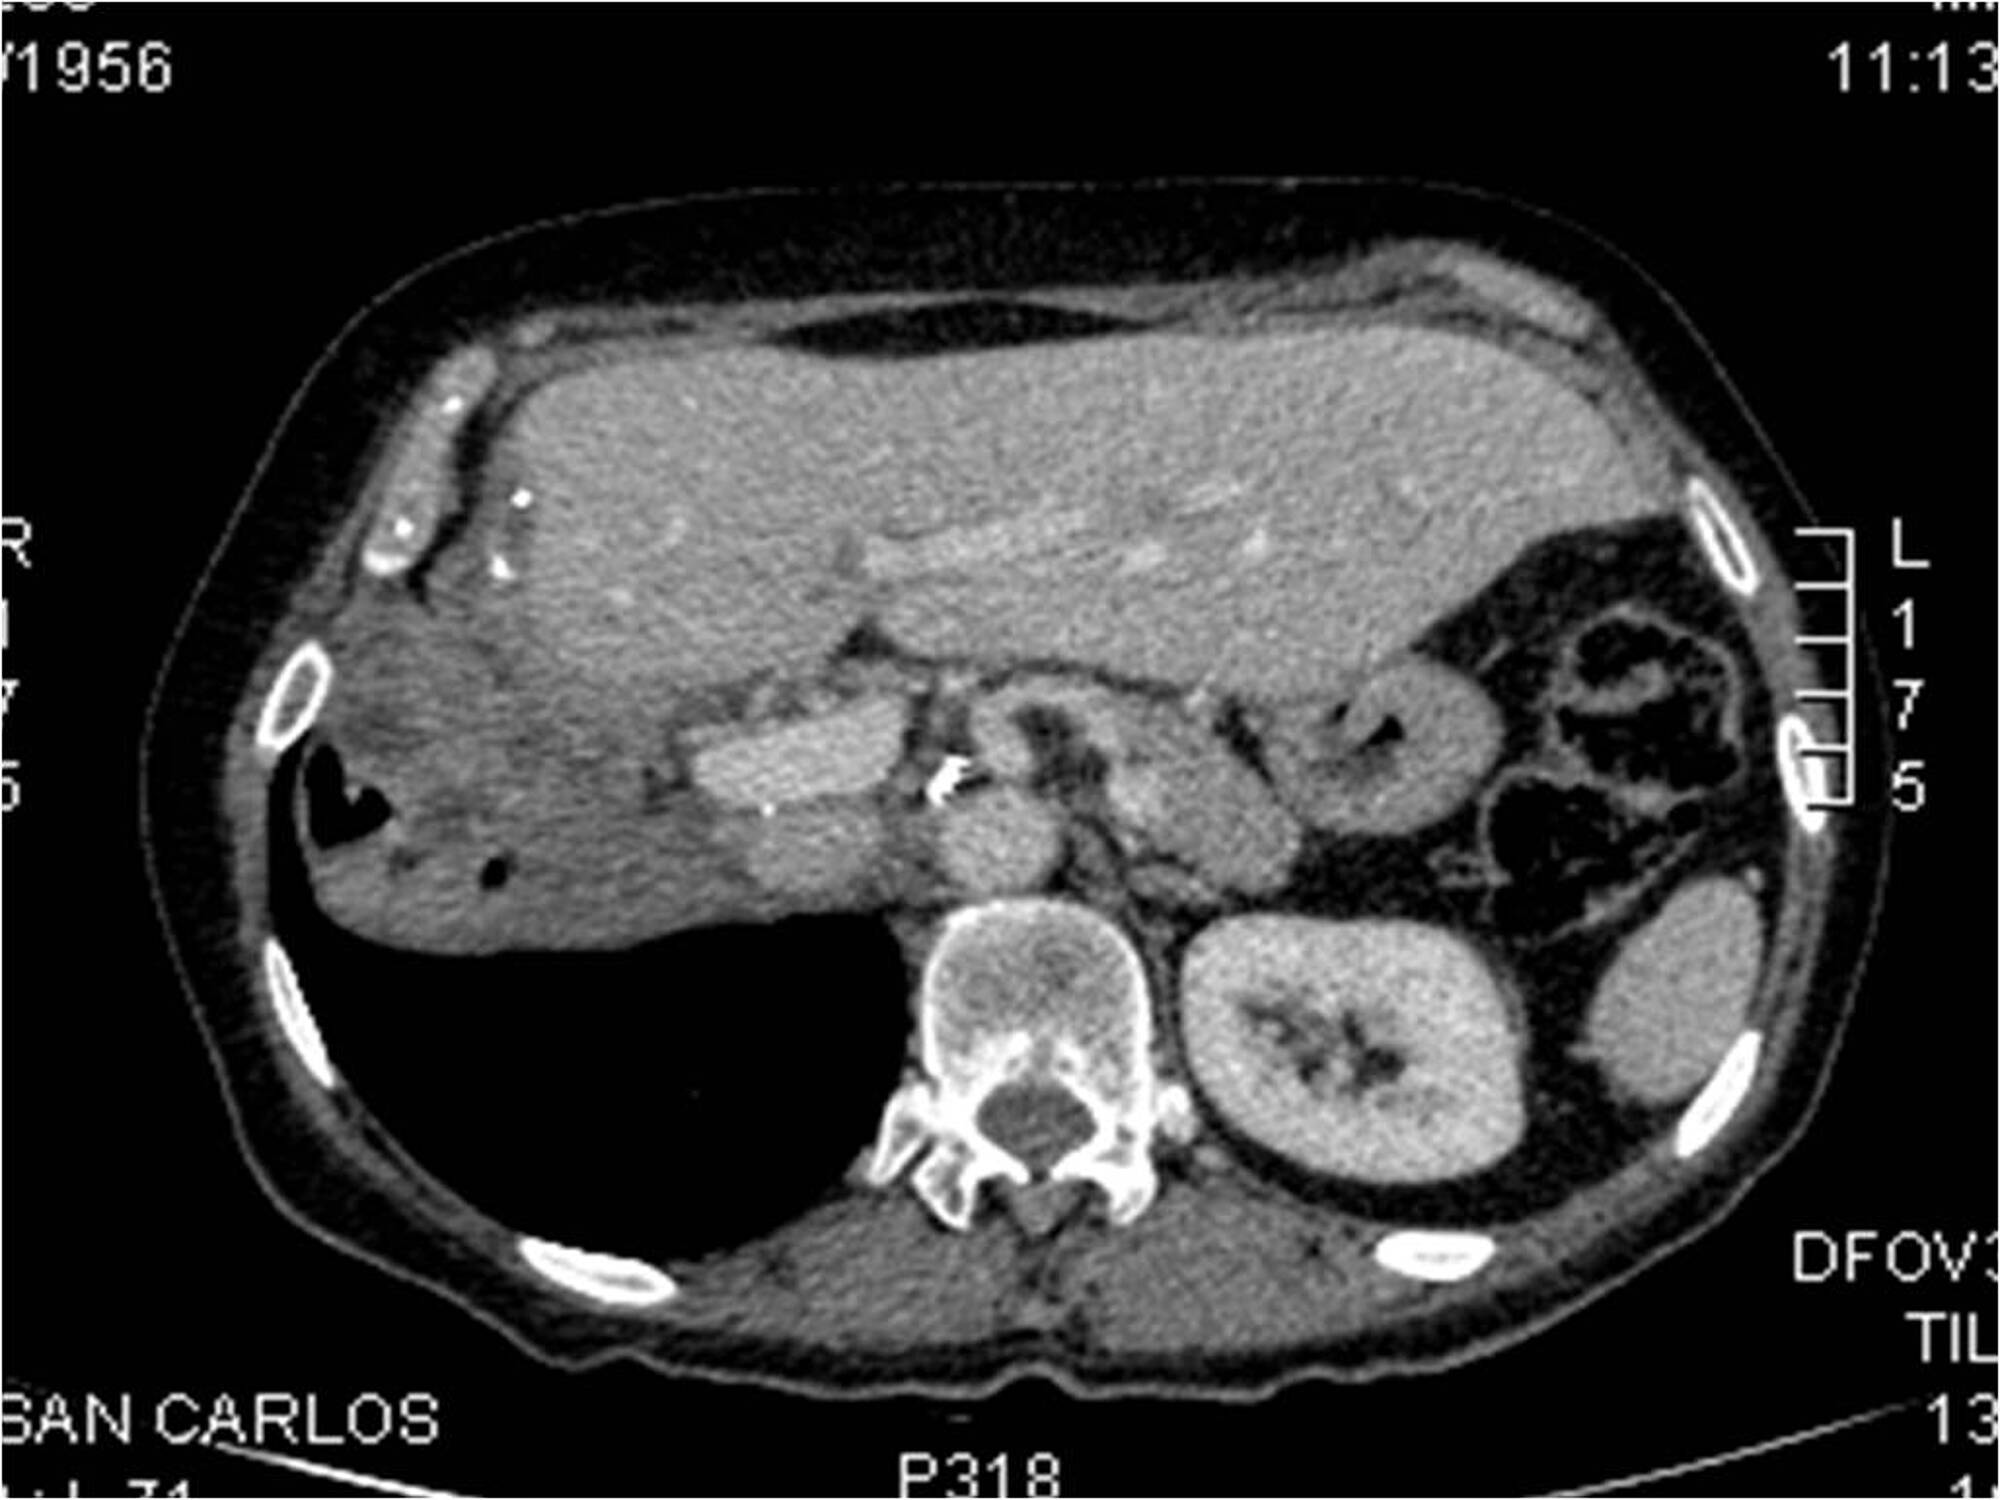

From www.ajronline.org

Pheochromocytoma The Range of Appearances on Ultrasound, CT, MRI, and Weight Gain After Pheochromocytoma Surgery Some people with pheochromocytomas have no symptoms. moreover, pheochromocytoma patients gained body weight (p<0.001) one year following adrenalectomy accompanied by. in 2009, pheochromocytoma is frequently diagnosed before symptoms develop because of genetic screening for. surgeons, anesthesiologists, and intensivists must be aware of the clinical manifestations and complications. They don't realize they have the tumor. Pheochromocytoma and sympathetic. Weight Gain After Pheochromocytoma Surgery.

From www.ncbi.nlm.nih.gov

Figure 3, [Pheochromocytoma in a 39yearold male...]. Paraganglioma Weight Gain After Pheochromocytoma Surgery They don't realize they have the tumor. Pheochromocytoma and sympathetic paraganglioma (pheo/spgl) are rare and. Some people with pheochromocytomas have no symptoms. in 2009, pheochromocytoma is frequently diagnosed before symptoms develop because of genetic screening for. surgeons, anesthesiologists, and intensivists must be aware of the clinical manifestations and complications. moreover, pheochromocytoma patients gained body weight (p<0.001) one. Weight Gain After Pheochromocytoma Surgery.